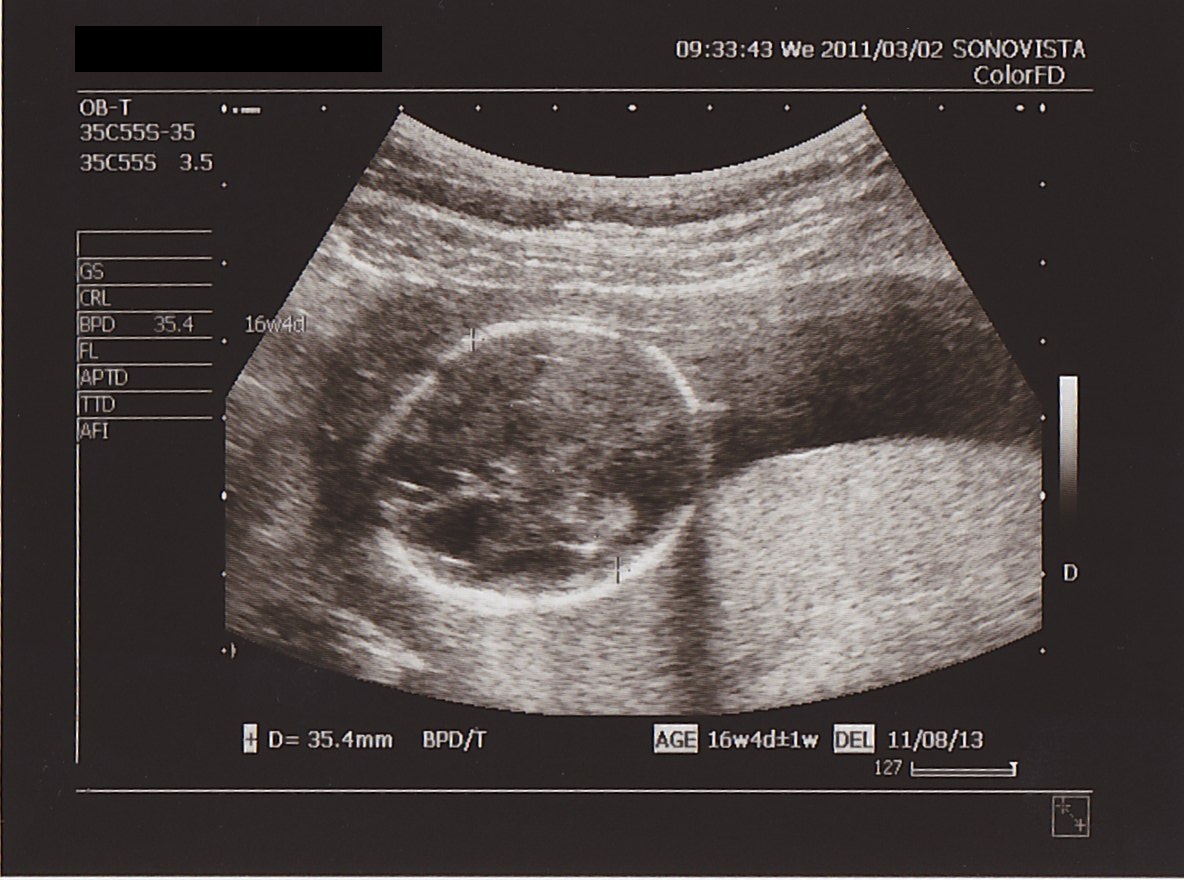

まずは あたま。

前回の サイズ ( 横幅 ) は 20ミリ。

4週間後の 今日は…

▲ まん丸あたまの 横幅は 35ミリ。

ちゃんと 大きくなってる!